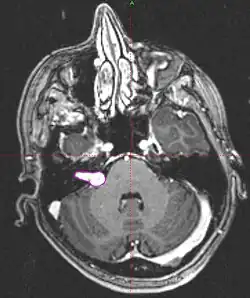

• Imaging: MRI with gadolinium can detect tumors as small as 1-2mm. Seen as an enhancing lesion “ice cream cone” in the region of internal acoustic canal or a “dumbbell” extending into the foramen magnum.